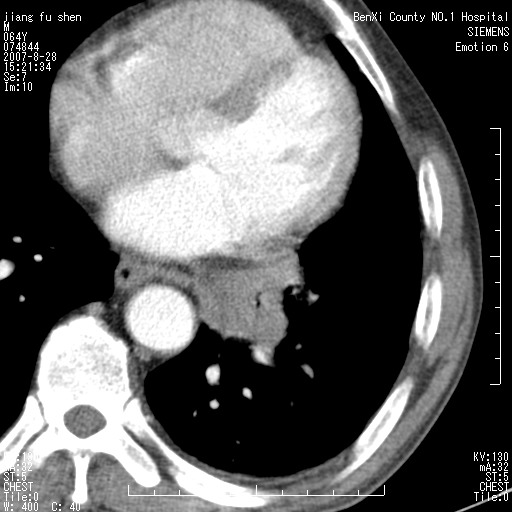

男、64、咳嗽、发烧一周、左肺呼吸音稍弱。既往肺结核,右手结核。

本次扫描患者未带原片,左肺下叶发现病灶。左肺上叶空洞,5组淋巴结肿大,1cm左右。

平扫20-33hu

增强31-33hu

1分半44-52

2分55-67

考虑左肺中央型肺癌并阻塞性肺炎

考虑左肺中央型肺癌并阻塞性肺炎,建议纤支镜检查

病灶边缘可见多量较长棘影及纤维条索状影,除外病灶边缘较光整,病灶有分叶表现,但多表现为较浅分叶,且向周围伸出之叶多呈尖角改变,且边缘较光整,病灶增强呈中度延时增强,且早期及中期仅轻度增强,结合患者病史,多考虑继发型肺结核,炎性增殖灶形成,不除外肺癌